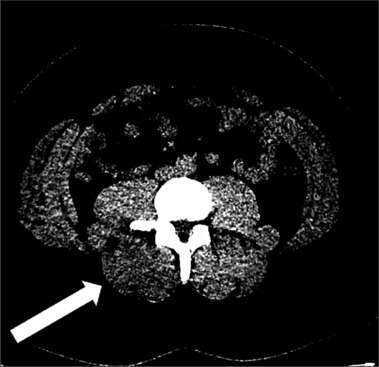

Lumbar paraspinal compartment syndrome is a rare pathology, with only 40 reported cases resulting from an increase in pressure within the muscle compartment. Symptoms typically involve pain and sometimes muscular deficits. The typical patient is a man who has undergone strenuous exercise, with few cases linked to the use of recreational drugs, such as cocaine or ketamine. We report the case of a 25-year-old man presenting to the emergency room with severe diffuse back pain who had recently consumed large amounts of cocaine, ketamine, and alcohol. The patient had diffuse muscular pain, increased serum creatine kinase (CK) levels, and a negative noncontrast abdominal computed tomography (CT), leading to the suspicion of crush syndrome. Over the following days, the patient's pain became more localized to the right paraspinal region, prompting a contrast-enhanced CT. This revealed signs of muscle swelling and edema of the paraspinal muscle, leading to a suspicion of compartment syndrome, which was confirmed by an intramuscular pressure measurement. The patient underwent a surgical fasciotomy. The patient went on to have an unremarkable recovery. Lumbar paraspinal compartment syndrome is exceedingly rare. Cocaine is known to cause rhabdomyolysis both indirectly, due to behavioral disturbances, and directly due to muscle toxicity. Similarly, ketamine use has also been associated with rhabdomyolysis. The rhabdomyolysis results in greatly increased CK levels, sometimes rising up to 100 00 U/L, which should normalize over the following days. A few cases of compartment syndrome, often localized in extremities, have been reported in patients presenting cocaine or ketamine-induced rhabdomyolysis. In this patient, the muscle swelling of the paraspinal muscle resulted in compartment syndrome. Patients who experience cocaine-related rhabdomyolysis have a tendency for nonspecific symptoms, which would match our patient's initial presentation. Although radiology's contribution to the diagnosis is limited, patients suffering from back pain or nonresolving rhabdomyolysis should be submitted to imaging, which may show signs of muscle swelling and edema on CT and magnetic resonance imaging. Diagnosis of compartment syndrome should be confirmed by measurement of muscle pressure, and if elevated, the patient should be proposed for fasciotomy.